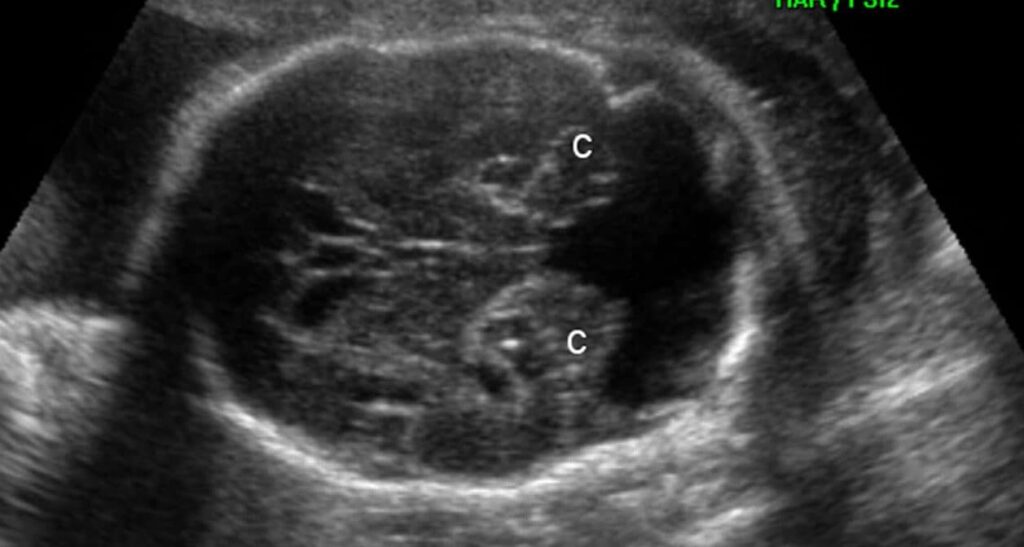

A malformação de Dandy-Walker é uma malformação cerebral caracterizada por hipoplasia ou agenesia do vérmis cerebelar e dilatação do quarto ventrículo, com formação cística na fossa posterior. O diagnóstico é realizado, na maioria dos casos, no período prénatal ou na primeira infância, decorrente de anormalidades no desenvolvimento fetal ou de sinais e/ou sintomas de hidrocefalia. Raros casos assintomáticos são descritos no adulto, quase sempre diagnosticados casualmente a partir de exames de imagem. Um diagnóstico diferencial importante da malformação de Dando-Walker é o cisto da bolsa de Blake.